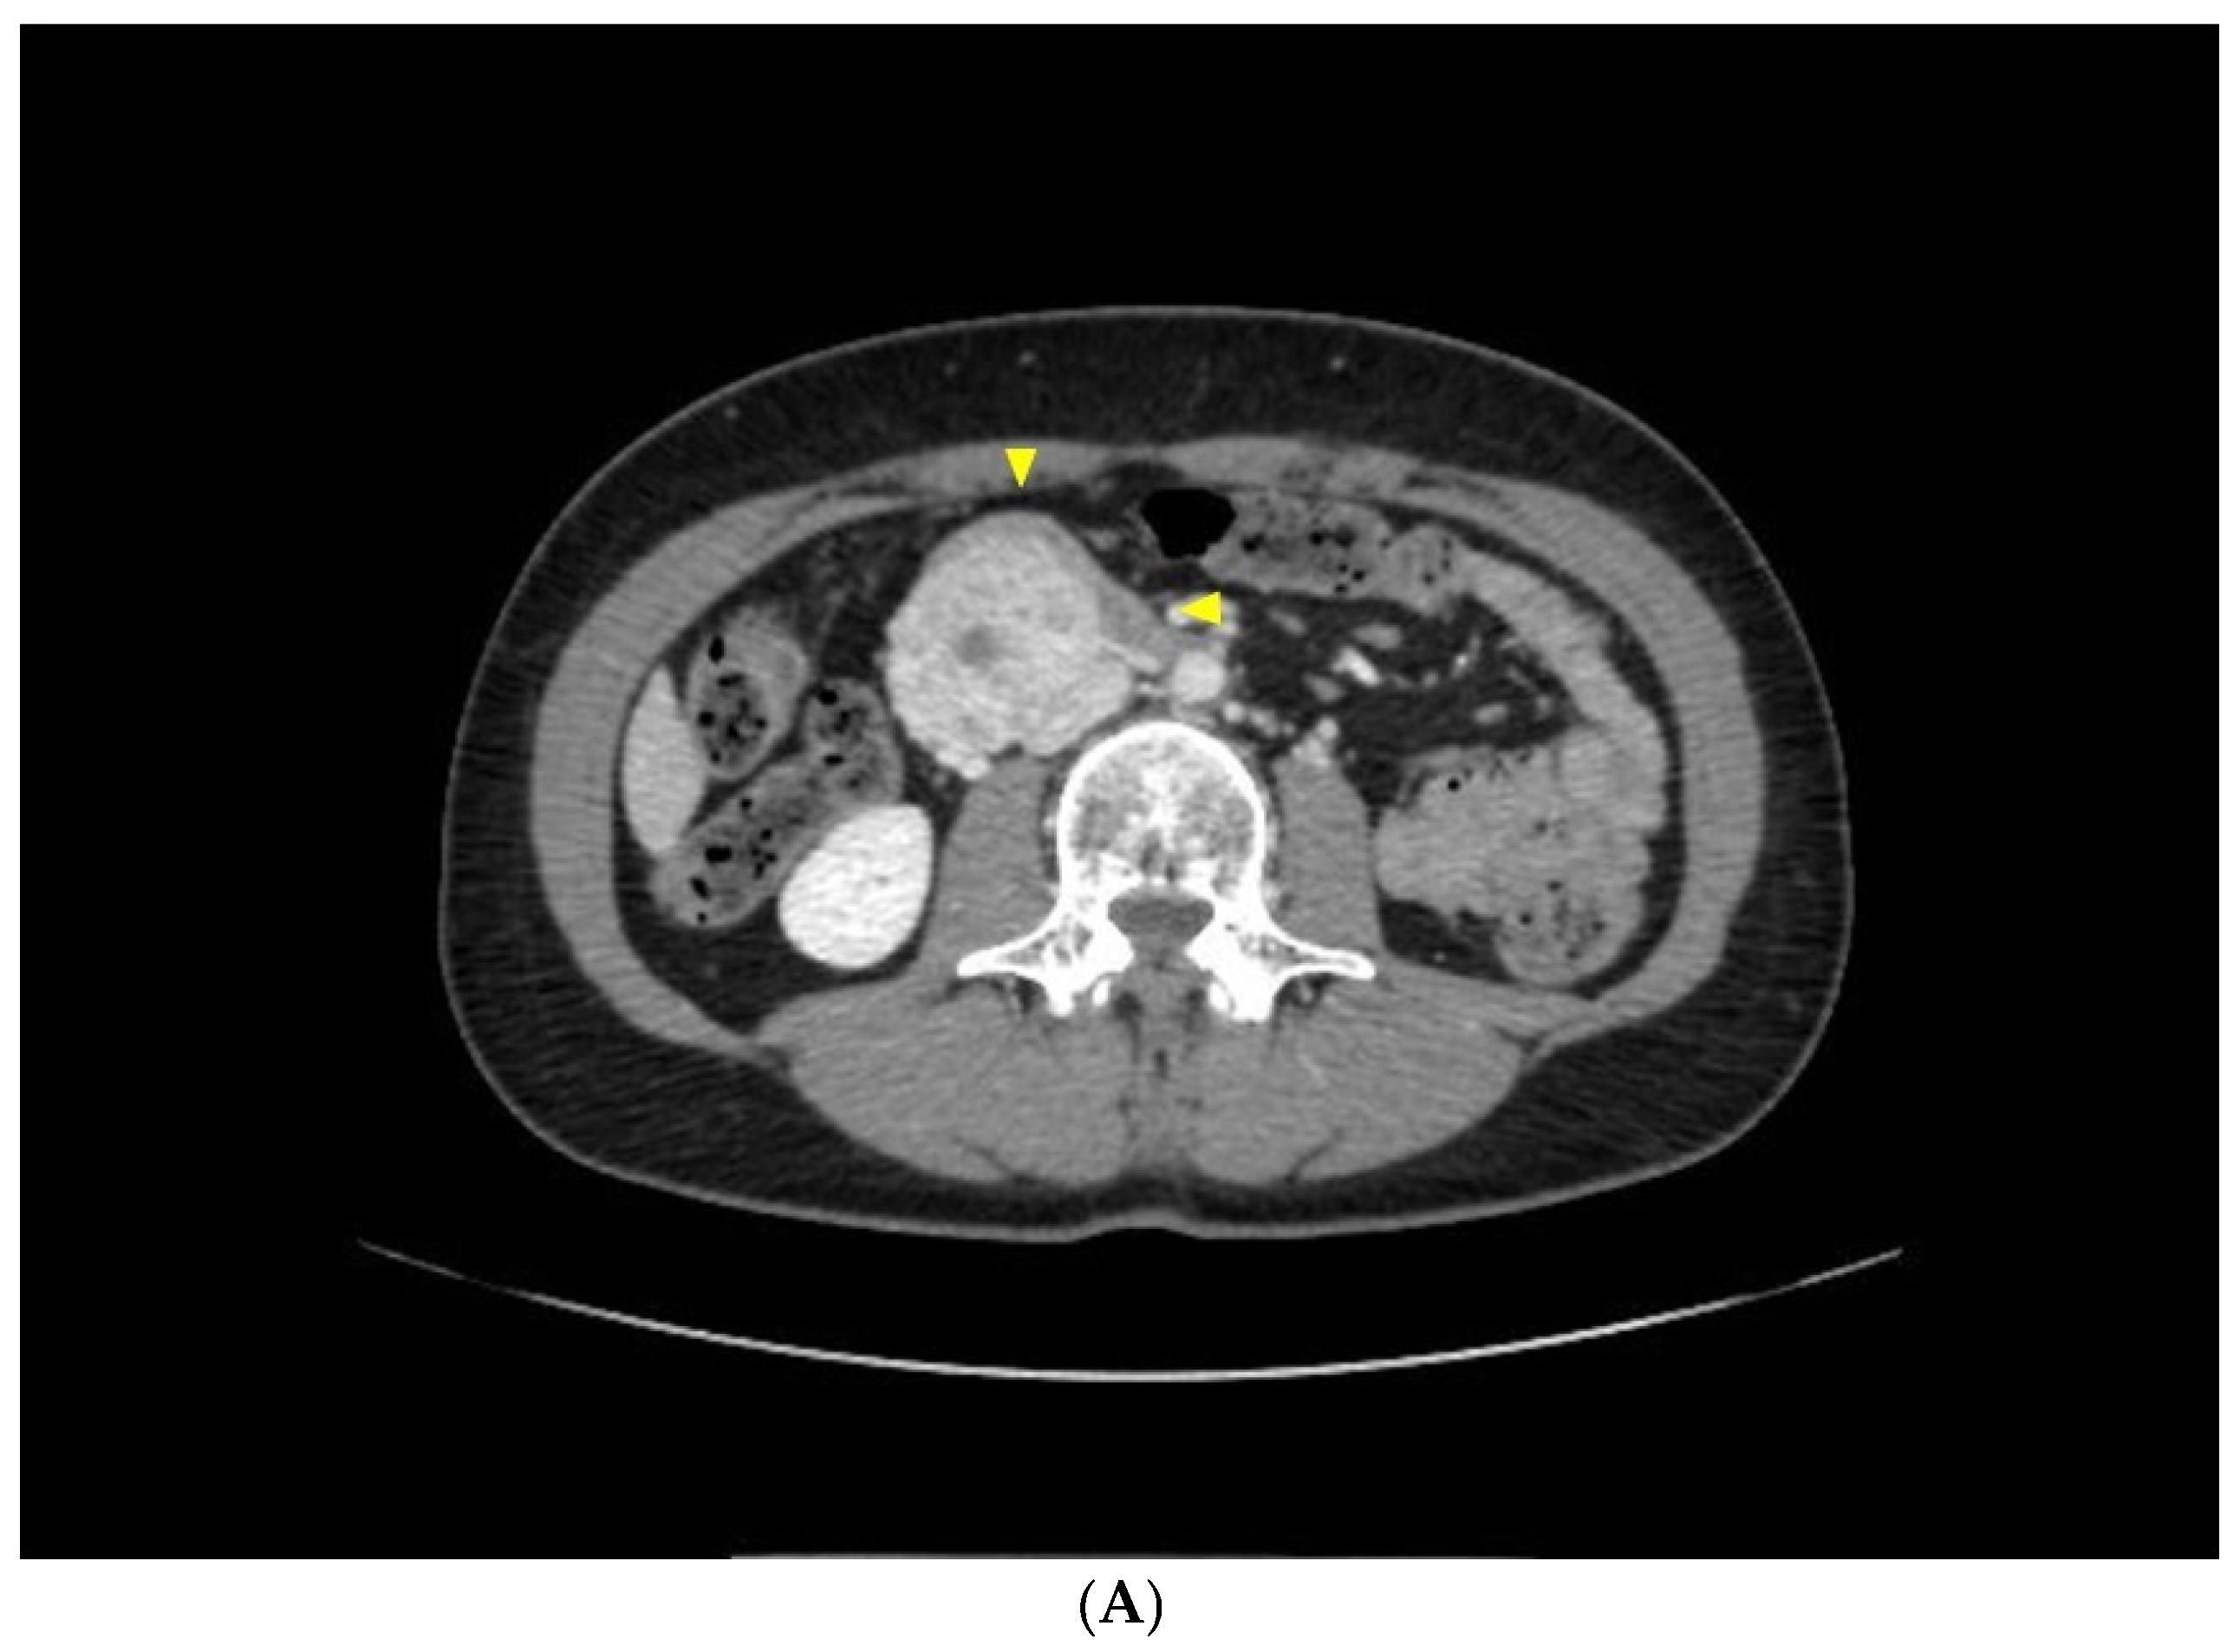

2.2. Case Report 2